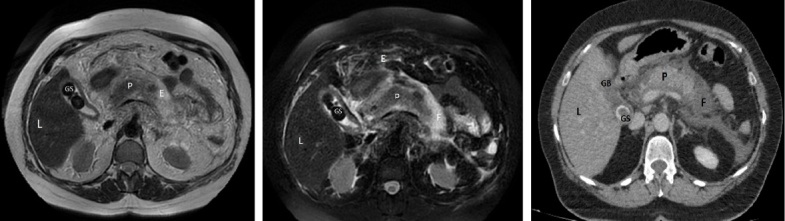

在胆道疾病中,胆结石的发病率在最近几年有所上升,仅在美国,就有约 6% 的男性和 9% 的女性患有胆结石。在西方国家,10%-20% 的成年人患有胆石症。虽然年龄的增长是胆结石形成的一个主要风险因素,但晚近的研究表明,胆结石的出现与症状出现的年龄下降有关。因此,我们面对的是一个表现为疼痛,有时还伴有功能障碍的年轻群体。根据统计分析,胆结石对美国等高度工业化国家的经济影响每年高达 65 亿美元。在这种情况下,适当的干预时机就成为一个重要的关注因素。本综述使用了 28 篇文章和专业文献。文章的选择以关键词为基础,关注超声波、CT 和核磁共振成像等影像学检查对胆石症患者诊断的有效性。由于无法对影像学检查技术进行直接比较,我们尝试确定每种影像学评估的敏感性和特异性。比较分析表明,P Kruskal-Wallis

From the category of biliary disease, gallstones registered an increase during the last years, approximately 6% of men and 9% of women being affected by the pathology in the United States only. In western countries between 10-20% of the adult population is suffering from cholelithiasis. Although increasing age is a major risk factor for their formation, late studies correlate gallstones appearance with an age decrease for the onset of symptoms. We therefore face a younger population manifesting pain and sometimes functional disability. In accordance with statistical analysis, the economic impact of gallstones in highly industrialized countries such as United States produces costs of up to 6.5 billion dollars annually. In this context, the appropriate timing for intervention becomes a factor of major interest. The present review uses 28 articles and specialized literature. Article selection was based on keywords and followed the effectiveness of imaging investigation such as ultrasound, CT and MRI for patients diagnosed with cholelithiasis. Since a direct comparison between the imaging investigation techniques is not concluding we have tried to establish the sensitivity and specificity offered by each imaging assessment. The comparative analysis revealed a p Kruskal-Wallis <0.001 for sensitivity and p Kruskal-Wallis=0.474 for specificity.